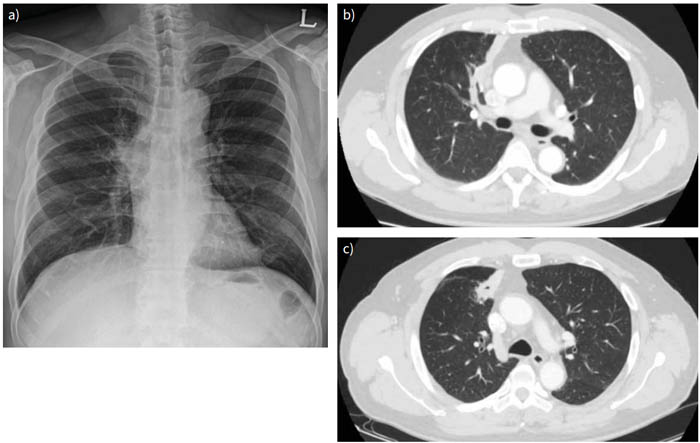

Các loài phổ biến nhất liên quan đến bệnh sán lá phổi là Paragonimus westermani, P. miyazakii, P. mexicanus và P. skrjabini. Sau khi bị nuốt vào cơ thể, ký sinh trùng sán lá phổi trưởng thành đi qua nhiều cơ quan hoặc mô và sau đó đến các mô phổi từ ruột non. Bệnh sán lá phổi có thể liên quan đến các tổn thương dạng nang và các nốt sần và 20% bệnh nhân có thể có các tổn thương do sán lá phổi không triệu chứng. Tràn dịch màng phổi đã được mô tả cụ thể với bệnh sán lá phổi và được báo cáo ở 40-70% bệnh nhân và có liên quan đến tăng BCAT. Tuy nhiên, bệnh sán lá phổi cũng có thể gây ra các nốt, thâm nhiễm và các khoang rỗng (Hình 4).

Dấu hiệu hình ảnh học phổ biến nhất là tràn dịch màng phổi liên quan đến sự thâm nhiễm lớn của BCAT.

Mặc dù biểu hiện kinh điển của nhiễm sán lá phổi là tổn thương phổi dạng khoang, nhưng chỉ có 5% bệnh nhân có dấu hiệu này. Một nghiên cứu về chụp cắt lớp vi tính ngực cho thấy các đám mờ dạng nốt (56,4%) và dấu vết di chuyển của sán (18,1%). Một biểu hiện hiếm gặp của hội chứng Loeffler cũng đã được mô tả với P. westermani.

Hình 4 (a) Hình chụp X-quang ngực theo hướng từ sau ra trước cho thấy có sự bất thường của rốn phổi bên phải ở một bệnh nhân nhiễm sán lá phổi Paragonimusspp.

(b) Hình ảnh CT cho thấy có một khu vực mô phổi bị hoại tử và phế quản bị tắc nghẽn ở phân đoạn trước của thùy trên bên phải.

Điều này có thể là dấu hiệu của các loại nhiễm trùng hoặc viêm như lao, actinomycosis, viêm phổi và ít có khả năng là ung thư phổi ở cùng bệnh nhân nhiễm sán lá phổi Paragonimus spp.

(c) Hình chụp CT ngực theo dõi sau 8 tháng điều trị bằng kháng sinh và liệu pháp kháng nấm không thấy dấu hiệu

cải thiện và bệnh nhân có dấu hiệu hình thành khoang trong phổi.